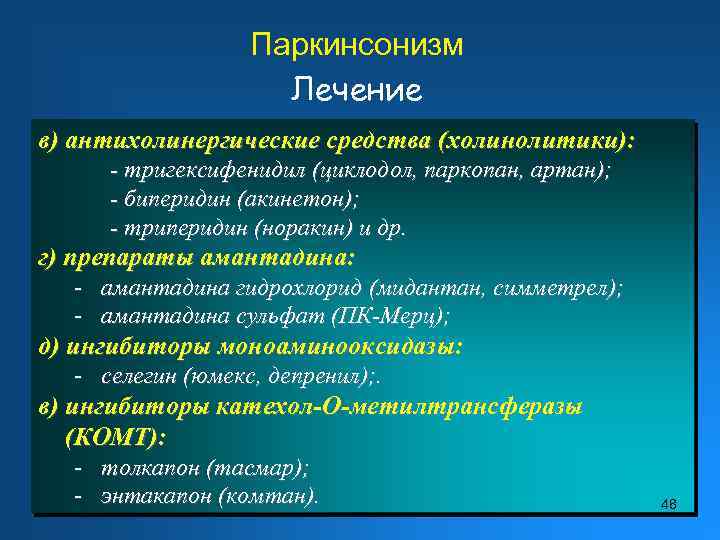

Пирамидная симптоматика в неврологии: ключевые аспекты